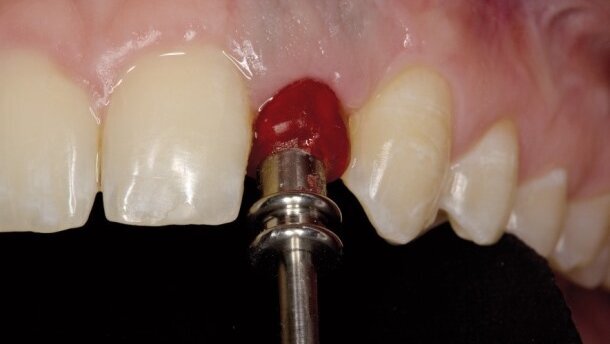

Po odsłonięciu implantu (Ryc. 10 i 11) rozpoczęliśmy kształtowanie profilu wyłaniania łącznikiem tymczasowym zespolonym z koroną tymczasową (Ryc.12). Na wizycie kontrolnej po założeniu korony tymczasowej stwierdziliśmy, że wskazana jest korekta girlandy dziąsłowej po stronie przeciwnej (Ryc. 13-16). Ryciny 17 i 18 pokazują dziąsło brzeżne nad implantem od strony przedsionka ukształtowane łącznikiem tymczasowym zespolonym z koroną tymczasową. Tak ukształtowany profil wyłaniania został zarejestrowany przy pomocy transferu wyciskowego zindywidualizowanego żywicą Patern Resin (Ryc.19). Transfer ten następnie użyłem w wycisku. Pozwoliło to technikowi doszlifować standardowy łącznik cyrkonowy do poziomu, na którym zaczyna on kontaktować z maską dziąsłową, tj. podpiera dziąsło pacjenta (Ryc. 21).